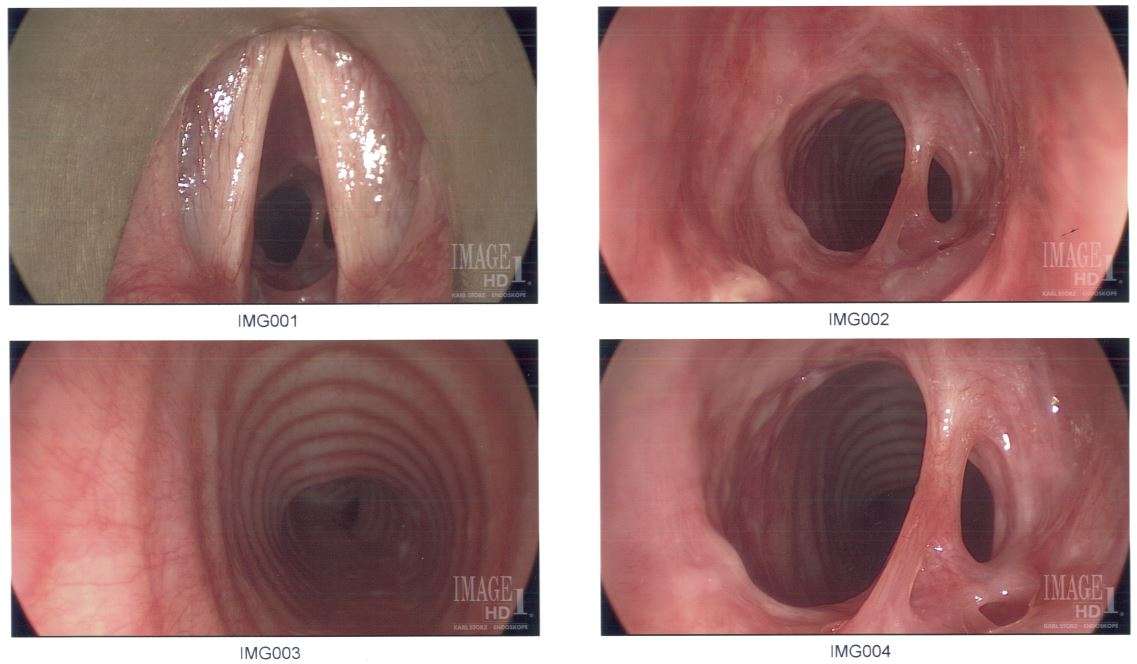

Subglottic stenosis is a congenital or acquired narrowing of the subglottic airway. Although it is relatively rare, it is the third most common congenital airway problem (after laryngomalacia and vocal cord paralysis). Subglottic stenosis can present as a life-threatening airway emergency. It is imperative that the otolaryngologist be an expert at dealing with the diagnosis and management of this disorder. Subglottic stenosis can affect both children and adults.

Subglottic stenosis can be of three forms, namely congenital subglottic stenosis, idiopathic subglottic stenosis (ISS) and acquired subglottic stenosis. As the name suggests, congenital subglottic stenosis is a birth defect. Idiopathic subglottic stenosis is a narrowing of the airway due to an unknown cause. Acquired subglottic stenosis generally follows as an after-effect of airway intubation, and in extremely rare cases as a result of gastroesophageal reflux disease (GERD).

Subglottic stenosis is graded from one to four based on the severity of the block.

Grade 1 - <50% obstruction, Grade 2 - 51-70% obstruction, Grade 3 - 71-99% obstruction, Grade 4 - no detectable lumen.